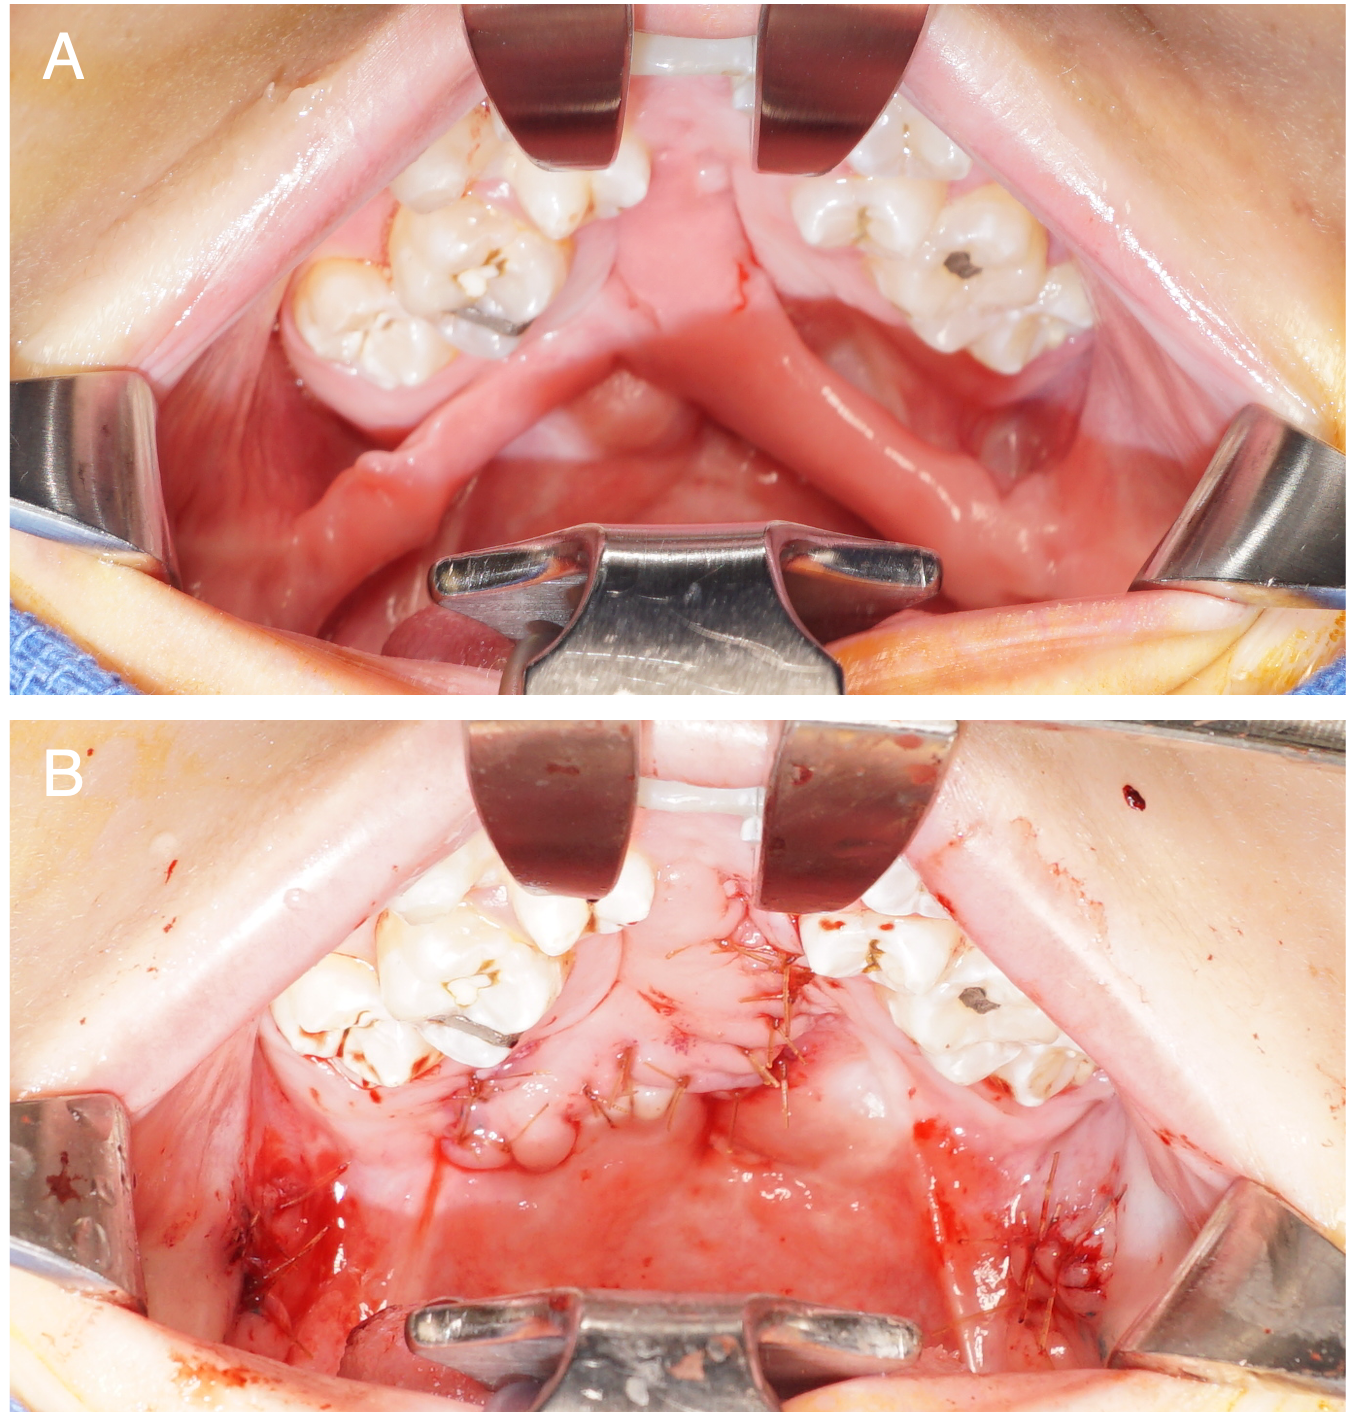

Seven patients underwent 7 fistula repairs using the FAMM flap (Table 2). The cohort consisted of 3 males and 4 females with repair; the median age was 10.8 years (range, 4.4-14.2 years). The median length of follow-up was 16 months (range, 5-182 months). Five patients had unilateral cleft lip and palate, and 2 patients had bilateral left lip and palate. The median hospital LOS was 34 hours (range, 30-36 hours). Flap debulking was performed in 6 cases, and the median time until debulking was 5.0 months (range, 3.1-25.0 months). Scar contracture was noted in 6 cases, with 4 requiring scar contracture release (Figure 7). The median time until contracture release was 4.2 months (range, 3.1-5.8 months). Successful fistula closure was achieved in 100% of the patients. No patients had flap dehiscence, necrosis, or infection.

Figure 7. (A) Postoperative scar contracture causing trismus following a facial artery musculomucosal flap. (B) Surgical release of the scar contracture with serial Z-plasties.